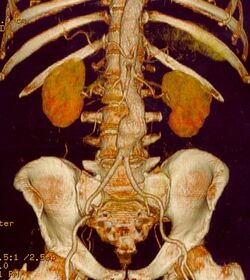

CT reconstruction image of an abdominal aortic aneurysm

The risk of rupture of an AAA is related to its diameter; once the aneurysm reaches about 5 cm, the yearly risk of rupture may exceed the risks of surgical repair for an average-risk patient. Rupture risk is also related to shape; so-called "fusiform" (long) aneurysms are considered less rupture-prone than "saccular" (shorter, bulbous) aneurysms, the latter having more wall tension in a particular location in the aneurysm wall.[10]